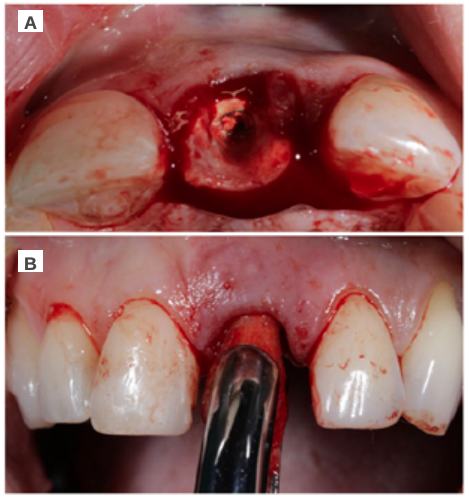

Clinical case: A 32-year-old female patient who attended for a possible root fracture of the upper left central incisor (ULCI), accompanied by a periodontal abscess at the bottom of the vestibule of the same tooth. A clinical and radiological examination established that the prognosis of the ULCI was unfavourable for conservative treatment. After evaluating the clinical features of the case, the treatment plan to extract the ULCI followed immediately by an osseointegrated implant (OII) and loading of a provisional prosthesis on the implant.

The physiological processes that take place after the extraction of a tooth are drastic, as they entail a series of modifications in the soft and hard tissues of the alveolar complex. Mainly, the microvascularisation of the architecture that surrounds the tooth suffers damage and atrophy that culminates in a decrease in the vascular supply provided by the periodontal ligament1-4. This results in a series of resorption processes discussed in this description of a clinical case.

Different protocols have also been established for the management of the anterosuperior aesthetic sector, in addition to performing the immediate implant and provisional crown, including placing material between the OII and the buccal cortical to minimise possible collapse and the management of peri-implant soft tissue8-11.